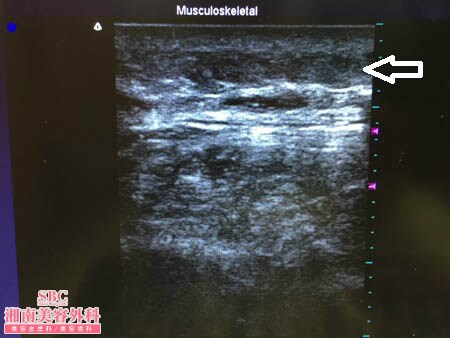

No.174557【脂肪吸引】【動画あり!】湘南美容外科・全ドクターの脂肪吸引総括指導医であるあの有名な根こそぎ竹田先生の劇的ビフォーアフター!香港在住の中国人の患者様の太ももを細くする!術中3Dタッチビュー・右太もも後面

患者様はこれと似た画像を

私のところに来るまでに

たくさん見てきました。

間違いなくご満足いただける術中になった

と自負しています。